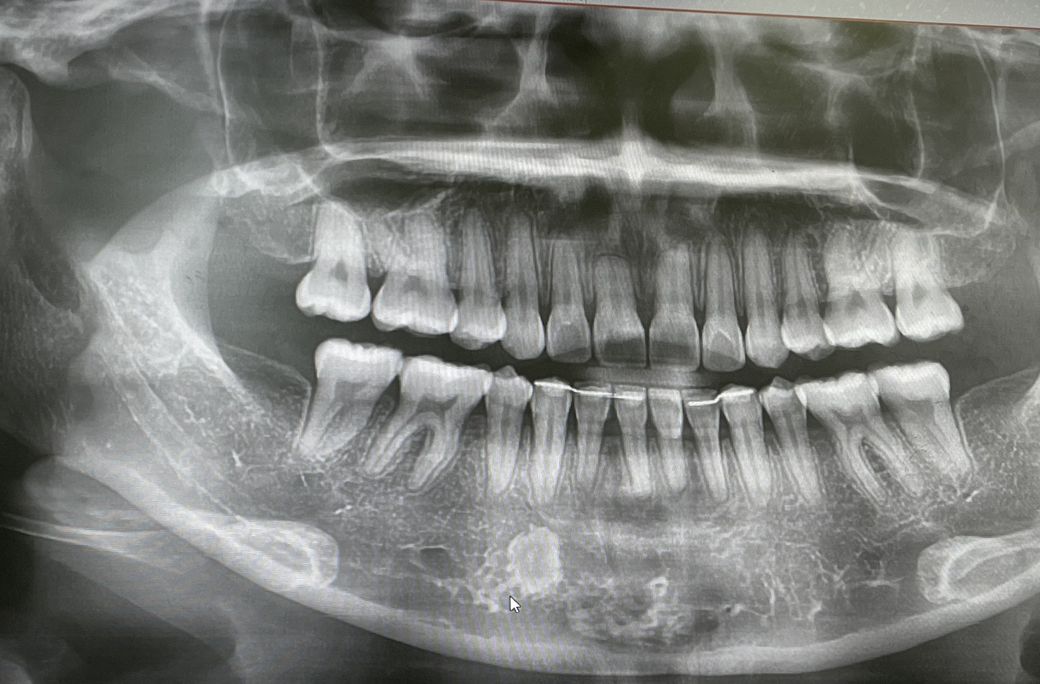

질문하신 내용에 대하여 아래와 같이 답변 드립니다.우선 엑스레이사진을 통해서 확인 가능한 충치는 치아와 치아사이의 인접면 우식과, 씹는 면의 깊은 충치입니다! 충치의 정도에 따라서 눈으로는 충치가 확인되어도 엑스레이로는 확인이 어려울수 있습니다! 또한 엑스레이에 여러가지 구조물의 중첩으로 인한 오진의 가능성도 있음을 미리 말씀드립니다!

현재 보여진 엑스레이 사진상에서 특별히 충치로 보여지는 부분은 없습니다! 다만 아래쪽 송곳니와 송곳니 뒤쪽 작은 어금니 옆면의 색이 어두워보여서 충치가 의심됩니다! 정확한것은 눈으로 보거나 기구로 확인해볼 필요가 있습니다!

위 앞니의 경우 치근의 흡수가 조금 보여집니다! 교정치료시 치근의 흡수는 일어날 수 있습니다. 지금 상태는 특별한 치료가 필요한 정도로 보여지지는 않습니다! 다만 정기적으로 검사해보고 만일 드물지만 치근흡수가 계속 진행되는 상황이라면 신경치료가 필요할수도 있습니다!

아래 앞니쪽에 안쪽에 붙이는 고정식유지장치가 일부 끊어진듯 보입니다! 이 경우 치아가 다시 틀어질수 있으므로 뺐다 끼울수 있는 가철식 유지장치를 사용하거나 끊어진 부위를 보강할 필요가 있습니다!

질문하신 내용에 대하여 아래와 같이 답변 드립니다.좌우측 3번 치아 즉 송곳니에 약간의 충치가 있어 보입니다. 하지만 방사선 사진 상으로는 정확히 진단하기 힘들며 임상 사진도 필요해보입니다. 전반적인 문제는 없고 뿌리에 염증도 없습니다. 교정도 잘되었는 것으로 판단됩니다.

질문하신 내용에 대하여 아래와 같이 답변 드립니다.사진으로 봤을때는 충치나 치료가 필요한부위는 없을것으로 보입니다.

다만 위앞니 2개는 교정에 의한 치아뿌리흡수가 보입니다. 크게 문제될것은 없습니다.